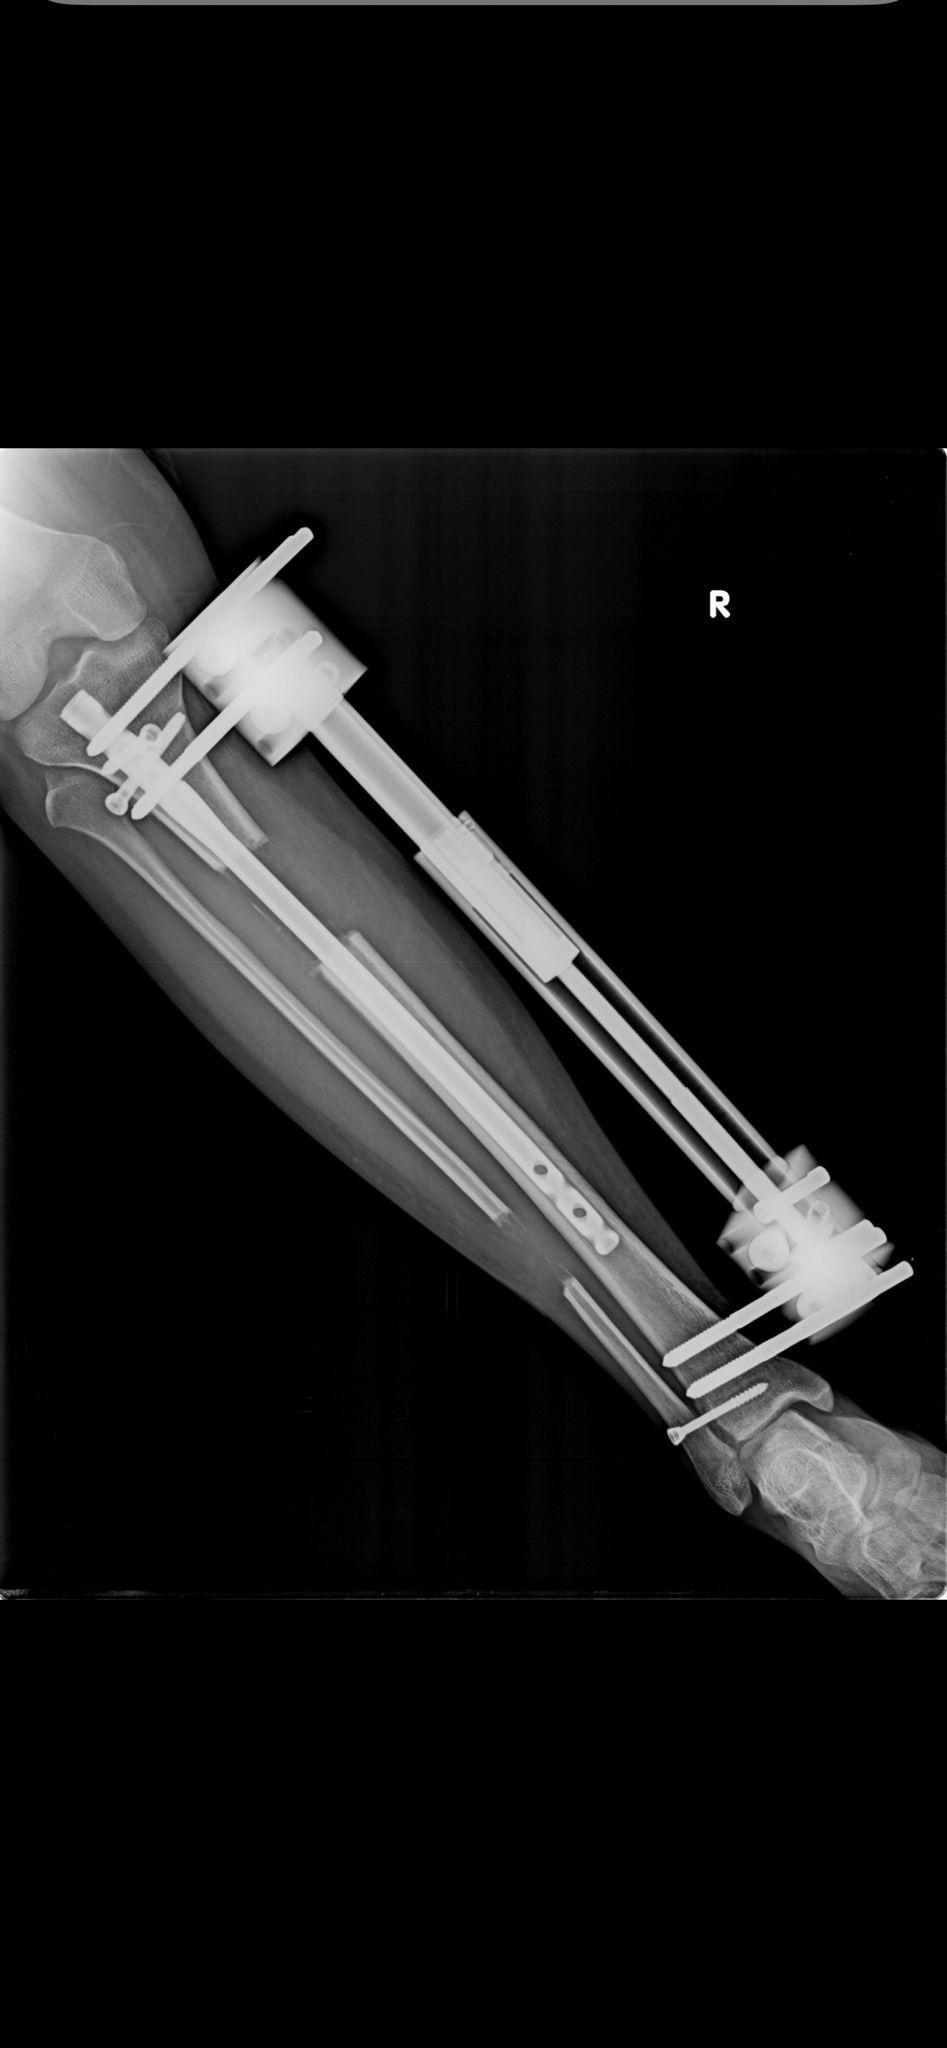

Lon Yöntemi

LON Yöntemi (Lengthening Over Nail) ile Femur ve Tibia Uzatma – Tıbbi Açıklama